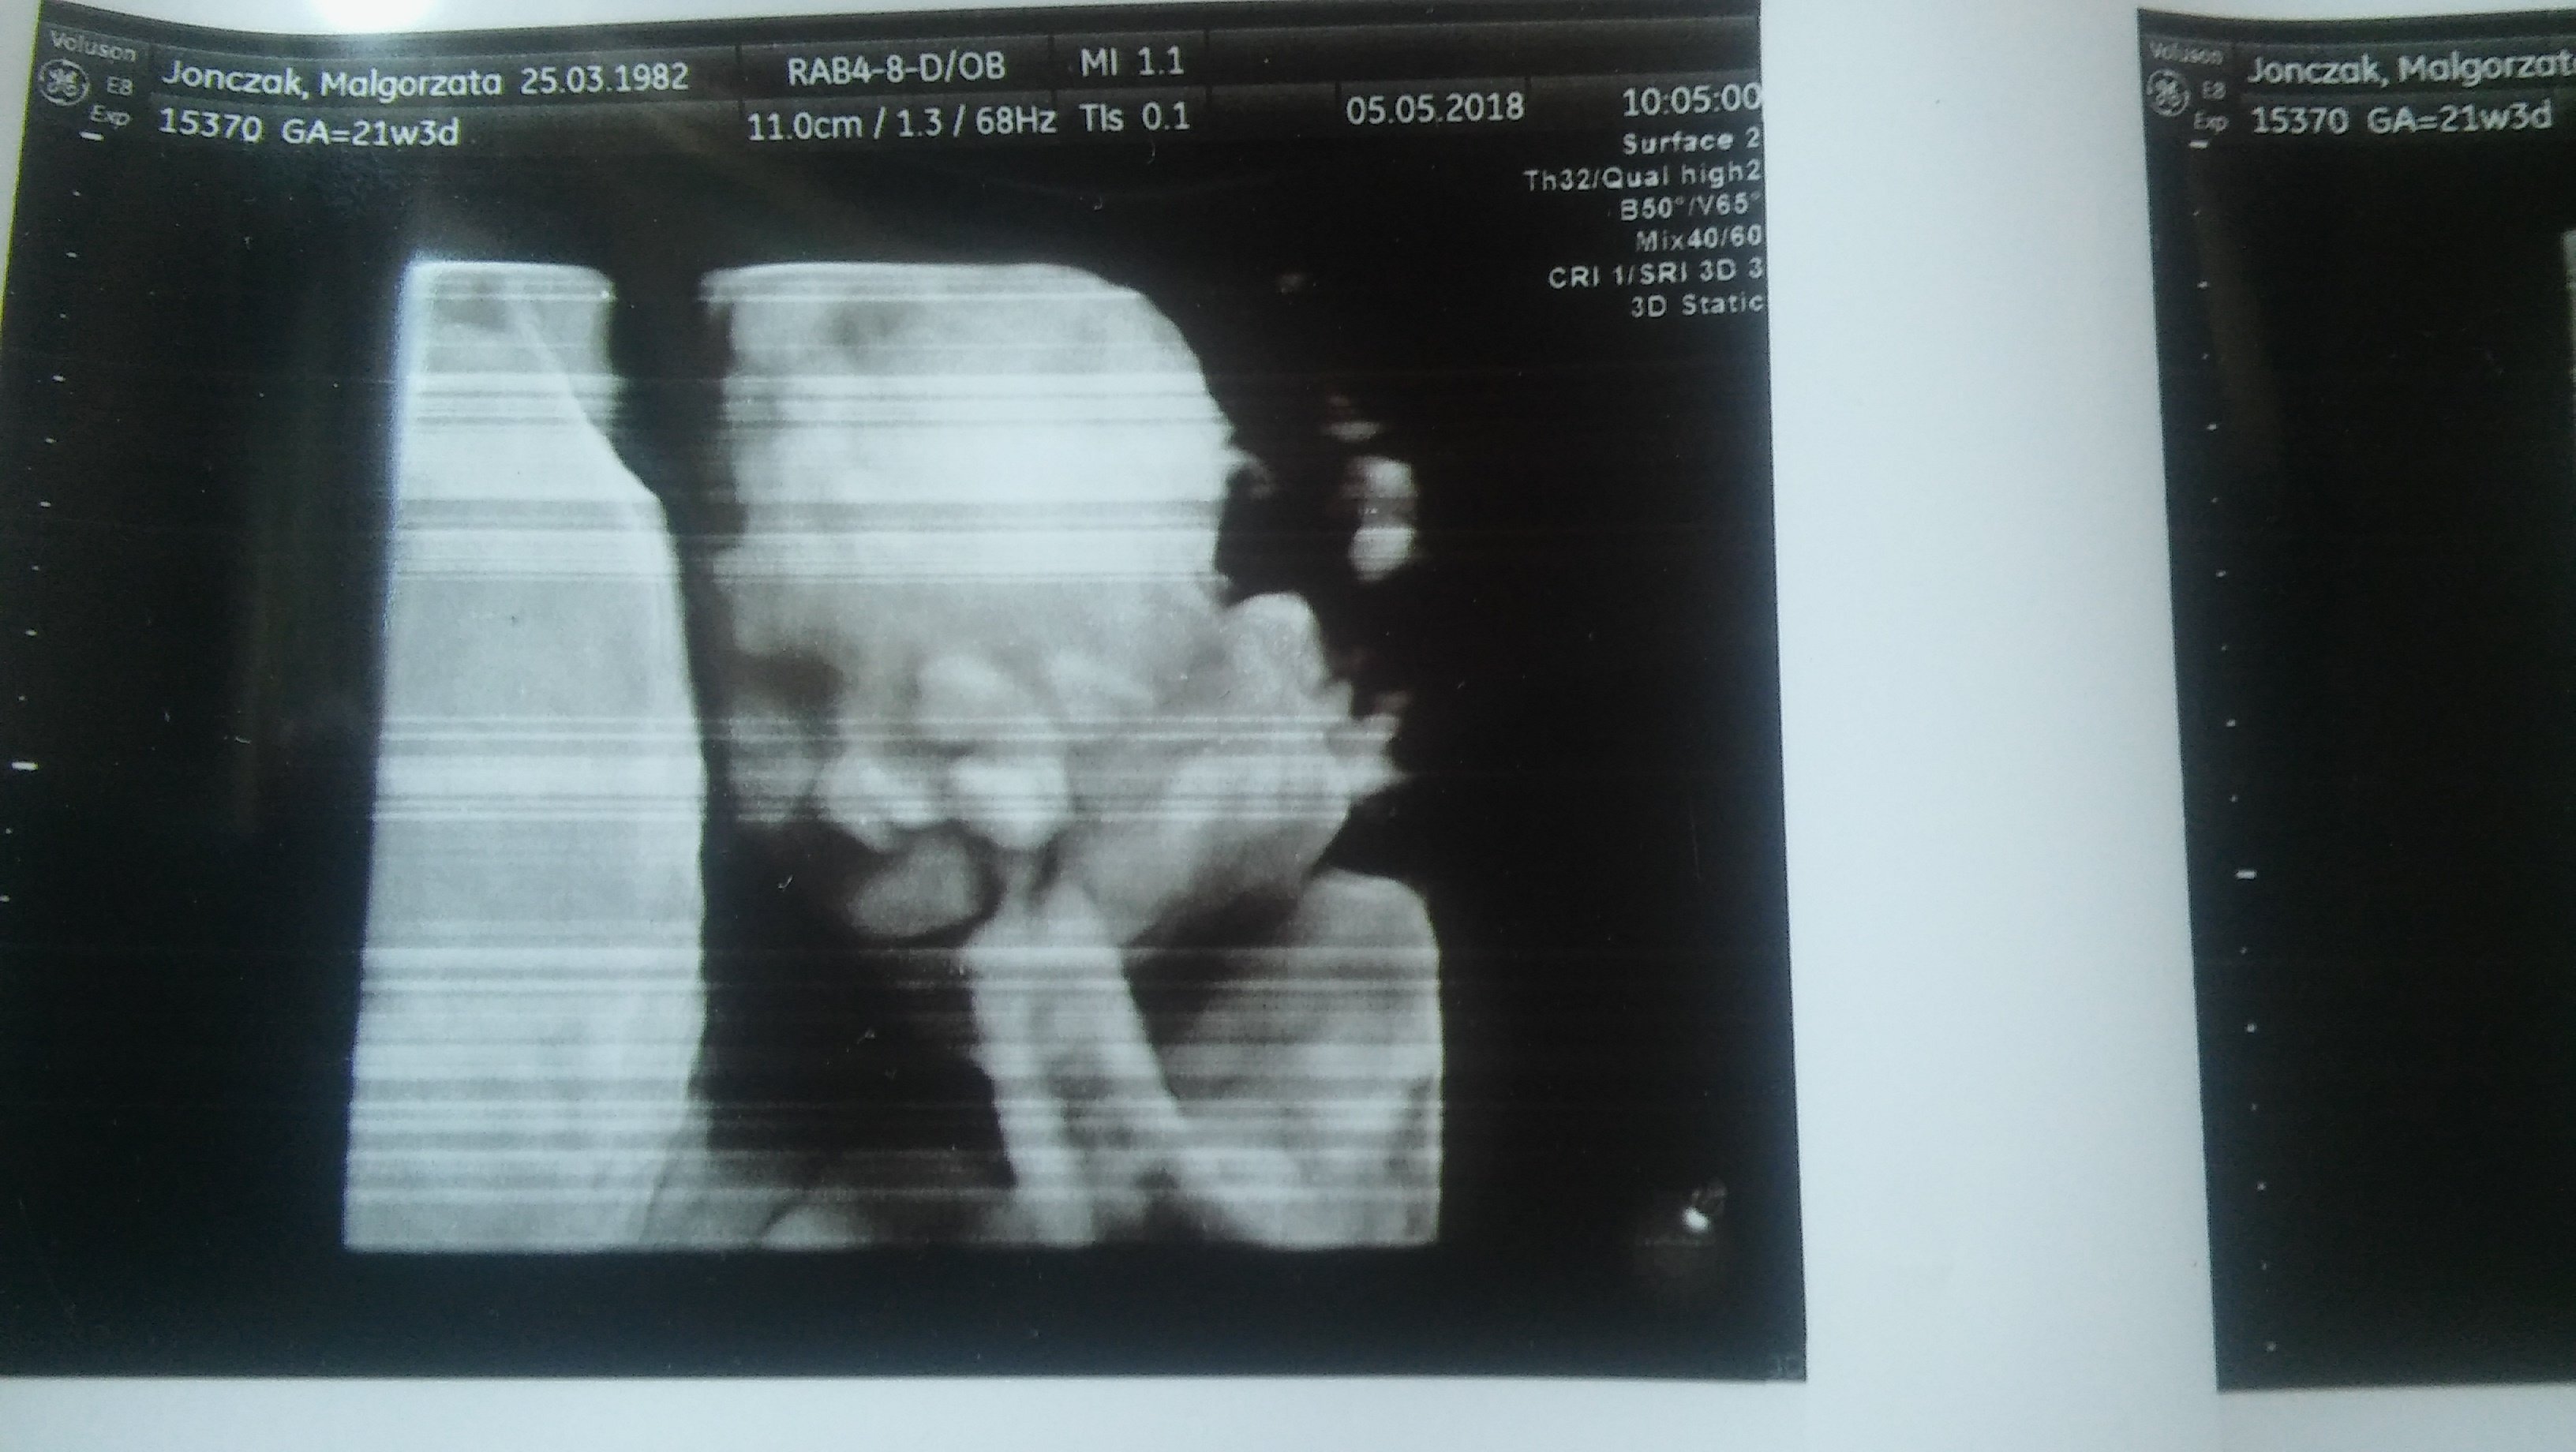

Pod koniec badania maleństwo zaczęło trzeć oczy i ziewać układając się do snu.

Pani pogratulowała Nam zdrowego ślicznego maluszka a ja przedstawiam Wam MIKOŁAJAZobacz załącznik 853658 Zobacz załącznik 853658

Zdjęcia fantastyczneA tu miki na 3d trze oczka i na normalnym profil